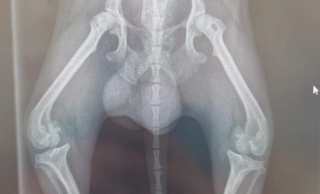

Jerry "marchait comme une araignée" au refuge. Le Chihuahua au pelage noir souffrait d’une luxation de la rotule, ce qui a provoqué une importante déformation de ses pattes arrière. Cette pathologie est douloureuse, et l’équipe du centre avait "du mal à imaginer la souffrance qu’il pouvait ressentir".

Sur une plateforme dédiée, l’organisation a rappelé l’histoire de Jerry et son problème. Elle a aussi glissé des photos de ses radiographies, montrant l’urgence de la situation. Elle s’est fixée pour objectif d’atteindre les 2200 euros, environ.